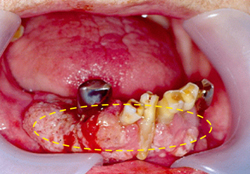

이 부위도 초기에는 잇몸에 발생한 염증이나 양성 종양과 유사하게 보일 수 있습니다. 진행되면 잇몸 주변의 치아를 둘러싸고 있는 치조골을 침범하기 때문에 치아가 흔들리게 됩니다. 더 진행하면 턱뼈를 침범하며 입술의 감각도 둔하게 됩니다. 간혹 치아를 뽑고 나서 상처가 아물지 않고 한 달 이상 지속적인 염증이 생기는 경우가 있습니다. 이러한 경우에는 잇몸에 발생한 구강암일 가능성도 있기 때문에 정밀한 검사를 받아보시는 것이 좋습니다.

[아래 잇몸에 발생한 구강암]

이가 흔들리는 원인은 잇몸질환으로 뼈가 녹아서 흔들리는 경우가 가장 많지만 갑자기 이가 심하게 흔들리면 잇몸에 발생한 암에 의한 증상일 수 있습니다. 또한 이를 뽑으면 대부분 2주면 아물지만 한 달 이상 이를 뽑은 자리가 아프고 아물지 않는다면 이것은 단순한 염증보다는 구강암에 의한 증상일 수 있습니다. 특히 윗니를 뽑고 아물지 않거나 심하게 아프다면 상악동이나 위턱에 발생한 암일 수도 있으므로 단순한 염증으로 생각하고 지체하기 보다는 전산화단층촬영 등의 정밀검사를 받는 것이 필요합니다.